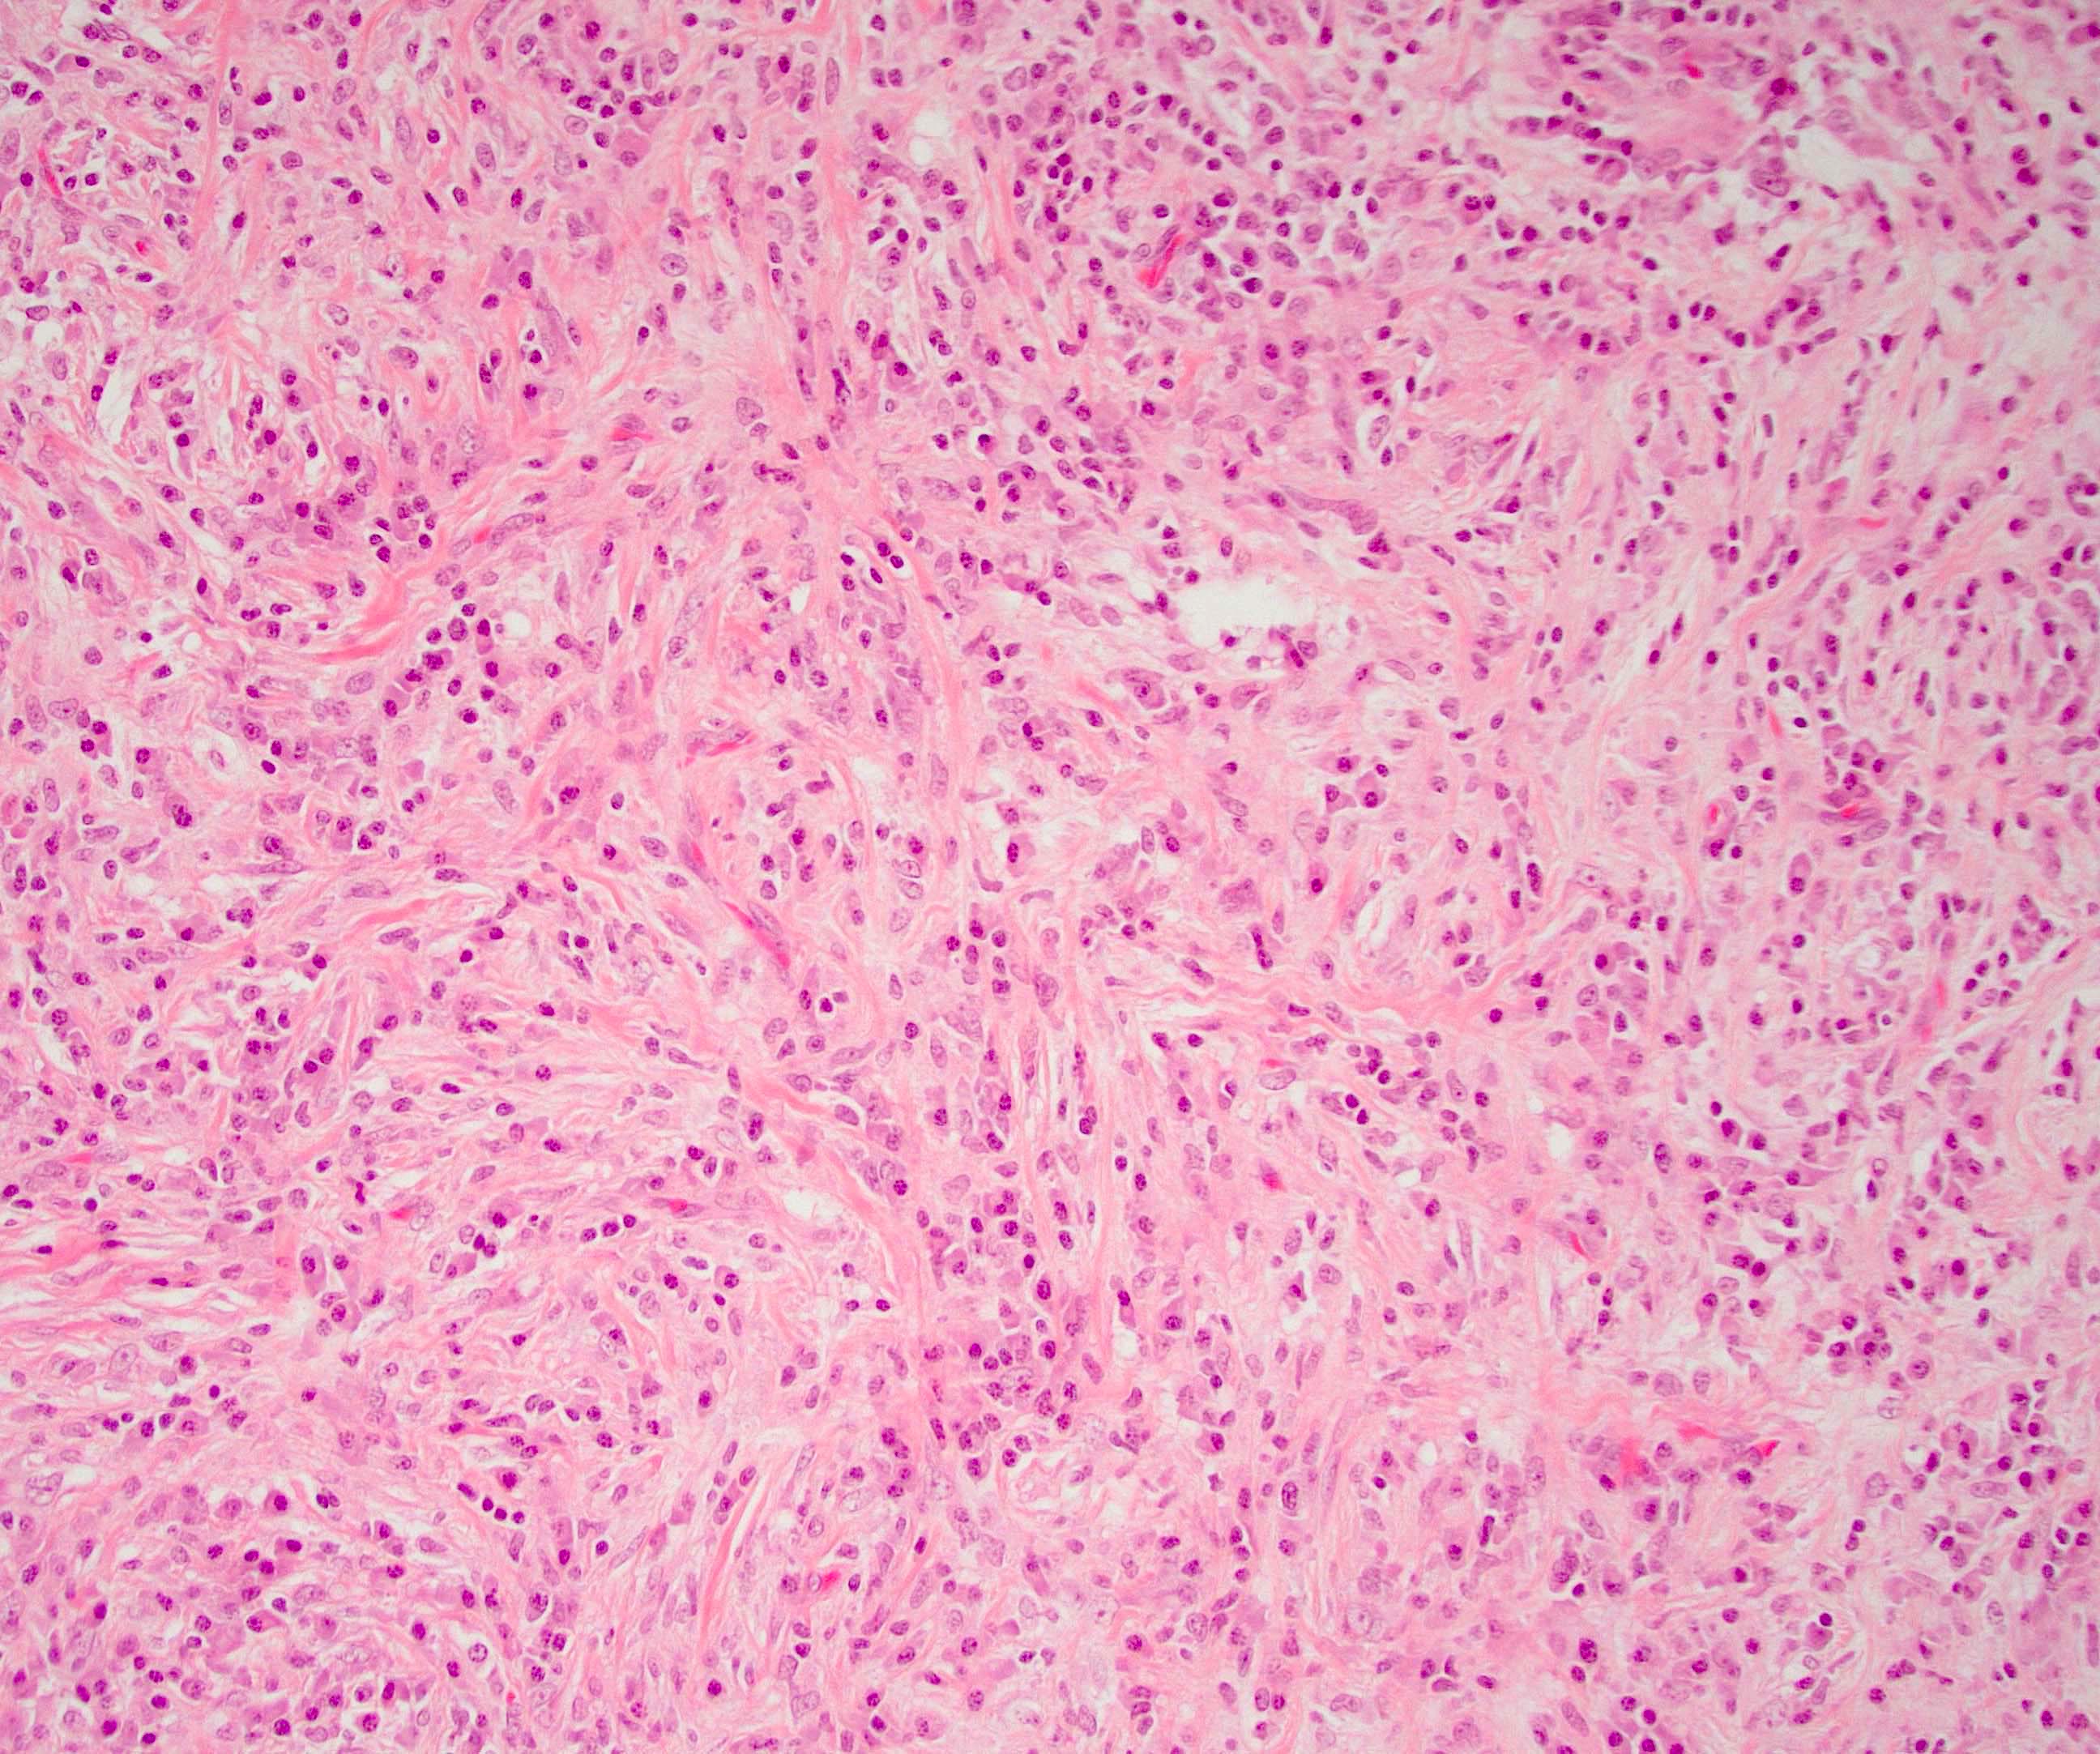

Microscopic (histologic) description

- Characteristic findings (at least 3 for level 1 criteria) (Pancreas 2011;40:352)

- Periductal lymphoplasmacytic infiltrate without granulocytic infiltration

- Obliterative phlebitis

- Storiform fibrosis

- Abundant (> 10 cells/high power field) IgG4 positive plasma cells

- Biopsy showing some but not all of the above features can be used as supportive evidence for the diagnosis of autoimmune pancreatitis (Pancreas 2011;40:352)

- Inflammation is localized within the pancreatic parenchyma and is centered around / within medium to large interlobular ducts, which causes shrinkage of the ductal lumen (Pathologica 2020;112:197)

- Inflammation can also be seen between the pancreatic parenchyma and peripancreatic adipose tissue (Pathologica 2020;112:197)

- Inflammation of the venous wall can progress to obliterative phlebitis with fibrosis of the lumen (Pathologica 2020;112:197)

- As the inflammation progresses, fibrosis becomes more diffuse, assuming a whorled or storiform pattern (Pathologica 2020;112:197)

- Perineural inflammation can also be present (Pathologica 2020;112:197)

Microscopic (histologic) images